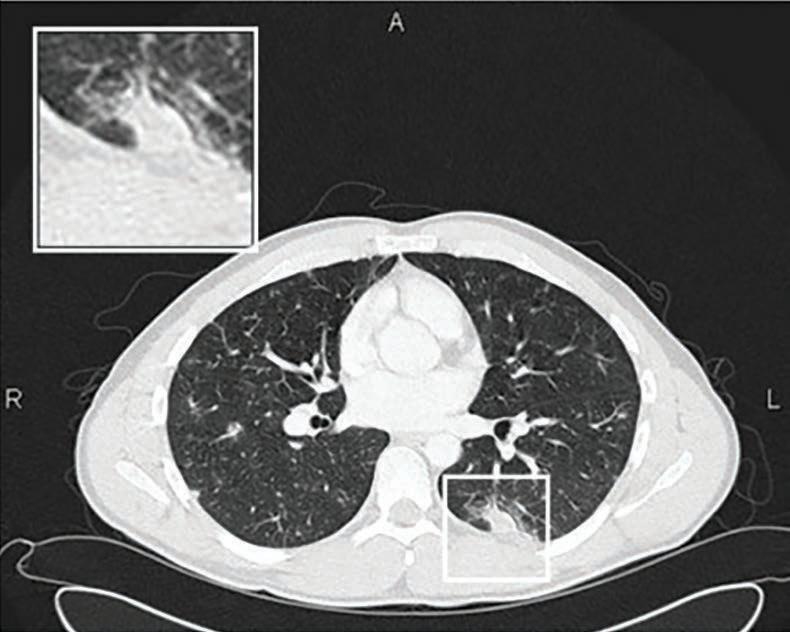

In 2025, the health system is still dealing with the legacy of decades of high rates of smoking and the demand for medical services is expected to rise with the launch of the National Lung Cancer Screening Program using low-dose CT scans to look for cancer in high-risk asymptomatic current and former smokers.

But now there are new kids on the block – nicotine products that can be legitimately used as second or third-line treatments to help people quit smoking, but have also developed into a lucrative new target for teenagers and young adults, many of whom have never smoked.

The Photon Counting CT machine at ChestRad requires ten times less radiation dose for lung cancer screening

All lung cancer screening bulk billed

1 Heismann, B Photon counting CT versus energy-integrating CT: A comparative evaluation Med Physics Dec 2024

Finding - Siemens Naeotom Alpha PCCT ten times more dose efficient for LCS than Siemens Definition Force

2. American Association of Physicists in Medicine Lung Cancer Screening CT Protocols V 6 0 November 2023

Finding - Siemens Definition Force four times more dose efficient for LCS than the next best CT machine